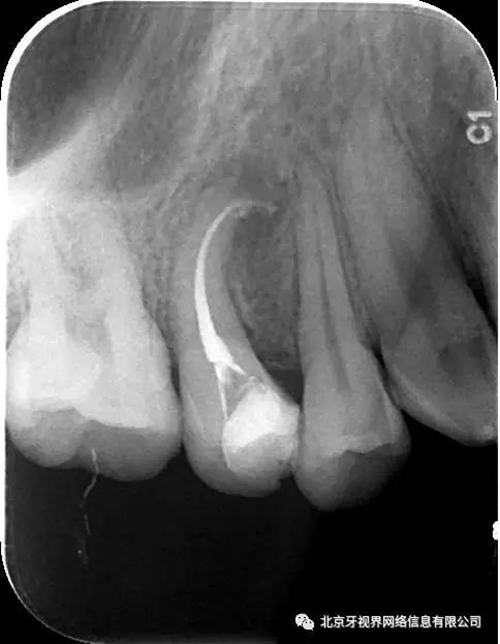

2次復(fù)診常規(guī)根備加根充(AH-plus糊劑加牙膠尖根充)

最后附帶近期彎曲根管的圖片